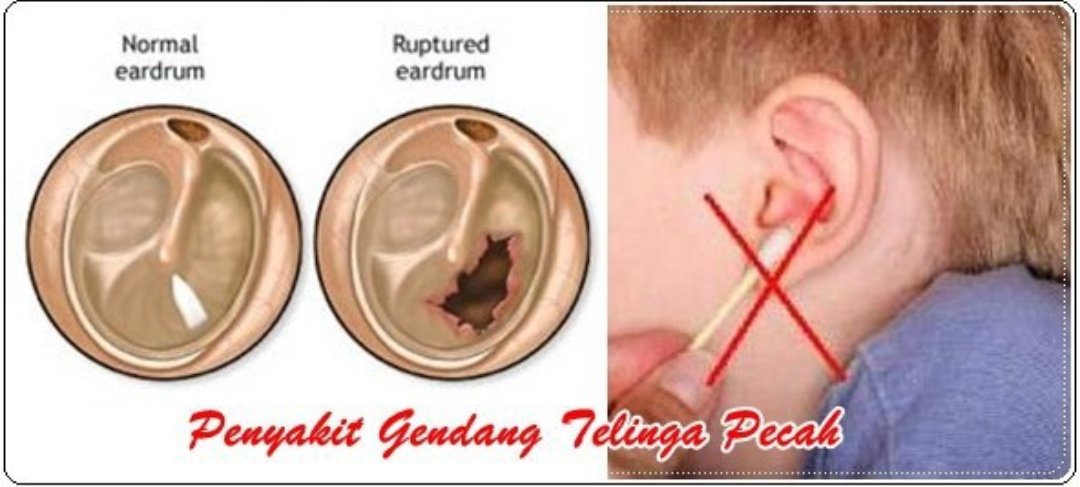

PETALING JAYA Tabiat suka membersihkan telinga menggunakan besi dan putik kapas menyebabkan seorang pesakit merana apabila gegendang telinganya pecah dan bocor. Sehingga istri Eryck Amaral itu memutuskan melakukan operasi. Gegendang telinga menyerap bunyi dan memindahkan bunyi tersebut kepada tulang.

Dr Mohd Shaiful Nizam Epul On Twitter 5 Antara Risiko Penggunaan Putik Kapas Besi Kunci Boleh Menyebabkn Cedera Pd Saluran Telinga Gegendang Telinga Bocor Pendarahan Dalaman Telinga Amp Jangkitan Nanah Pd Telinga Medtweetmyhq

Dr Mohd Shaiful Nizam Epul On Twitter Puan Gegendang Telinga Puan Dah Bocor Itu Sebab Kerap Keluar Nanah Kata Saya Owh Apa Perlu Saya Buat Doktor Balas Pesakit